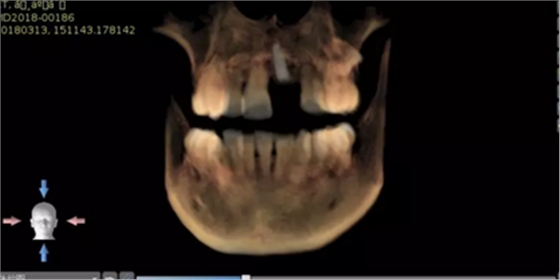

術(shù)后CT